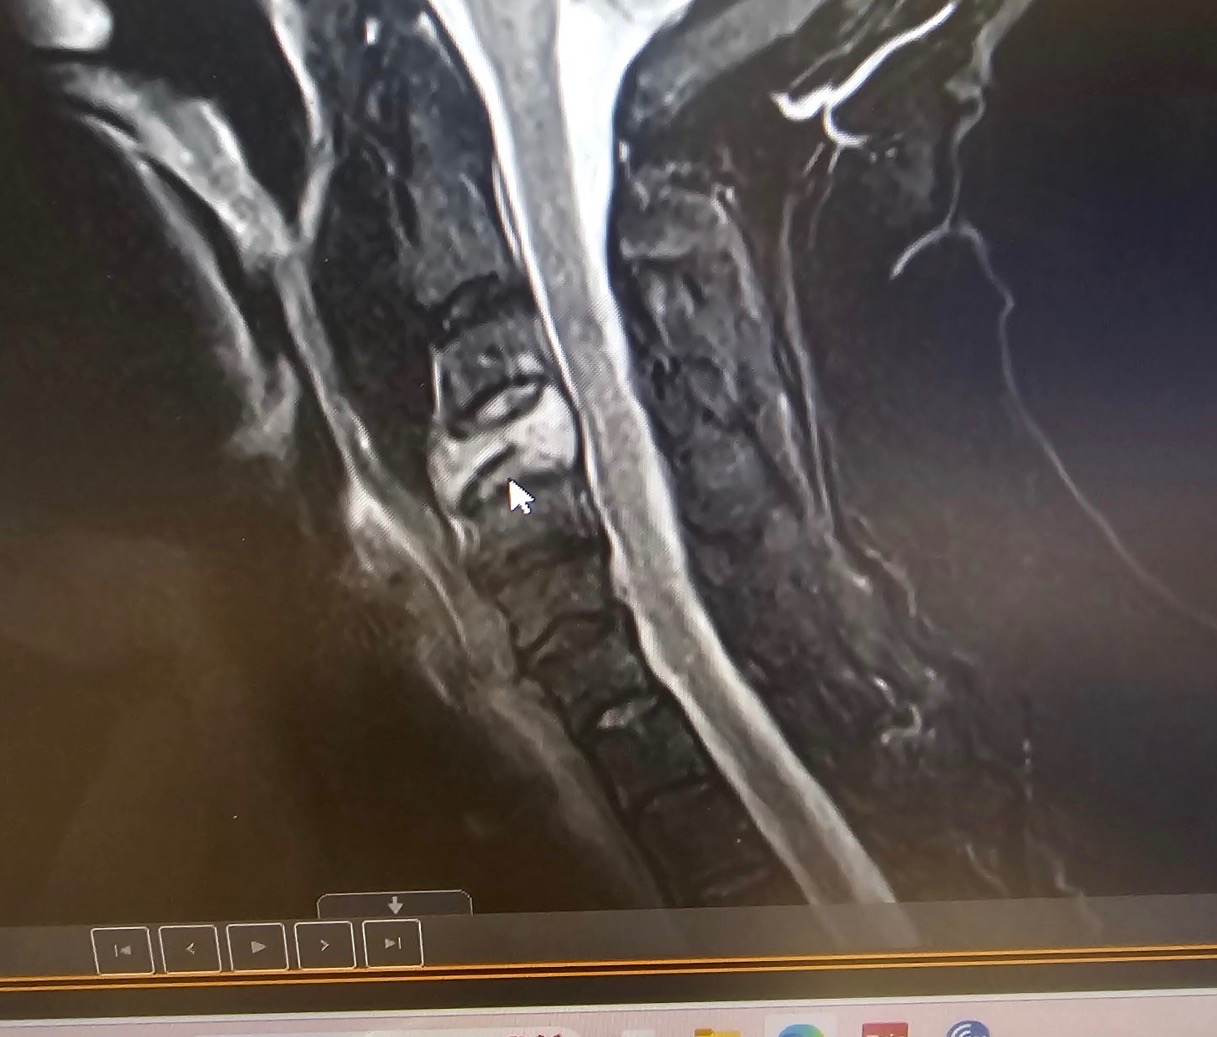

Recently, my doctors discovered significant damage in one of the vertebrae in my neck. I’ll be having surgery to remove the bone, replace it with titanium, and biopsy it to determine whether the damage is cancer-related. After I recover from that procedure, I’ll begin treatment for my breast cancer as well.